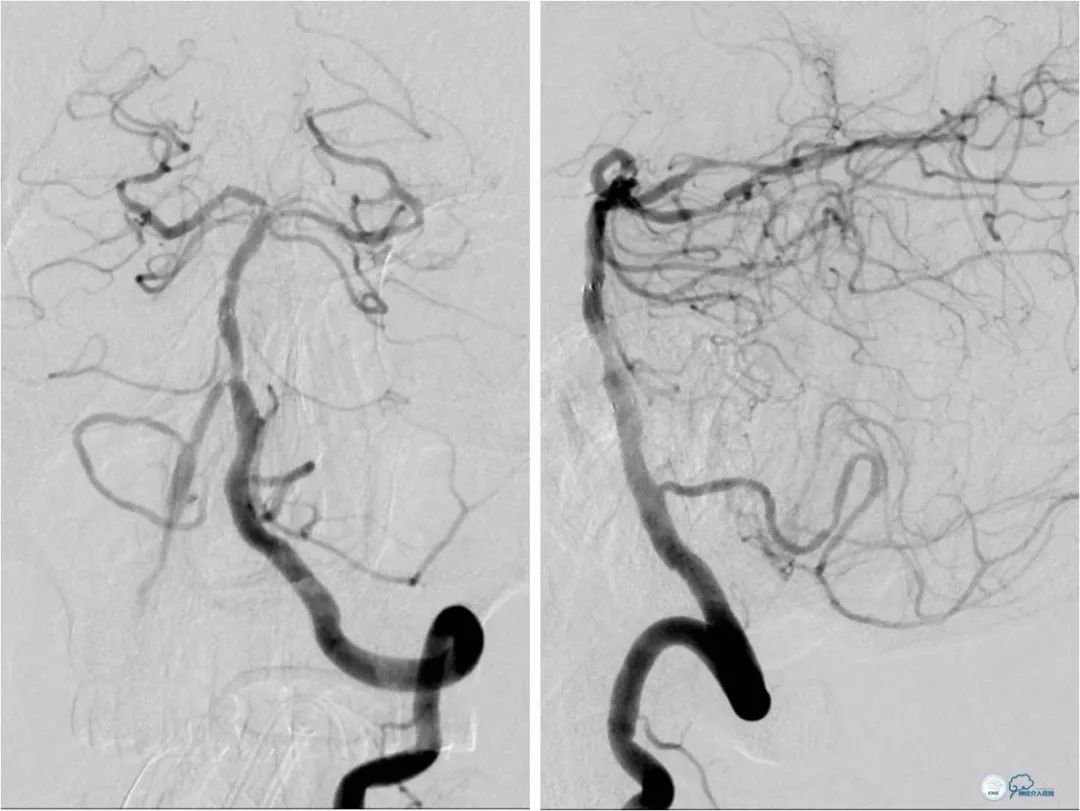

全麻下右股动脉入路,将6F导引导管至左锁骨下动脉近椎开口处, Transend微导丝(0.014″,300cm)放置于左椎动脉V2段,先用Ultra soft SV球囊(3×20mm)预扩张病变(图10)。

图10

其后置入Blue球扩支架(5×15mm),再跟进导引导管至左椎动脉V2段(图11)。

图11

此时造影示基底动脉重度狭窄(12)。

图12

将Transend微导丝(0.014″,300cm)在Echelon-10微导管帮助下放置于左大脑后动脉P2段,予以Gateway球囊(2×9mm)预扩张病变(图13)。

图13

后置入Wingspan自膨式支架(3.5×15mm),造影提示支架释放后支架贴壁良好,前向血流TICI 3级(图14)。

图14